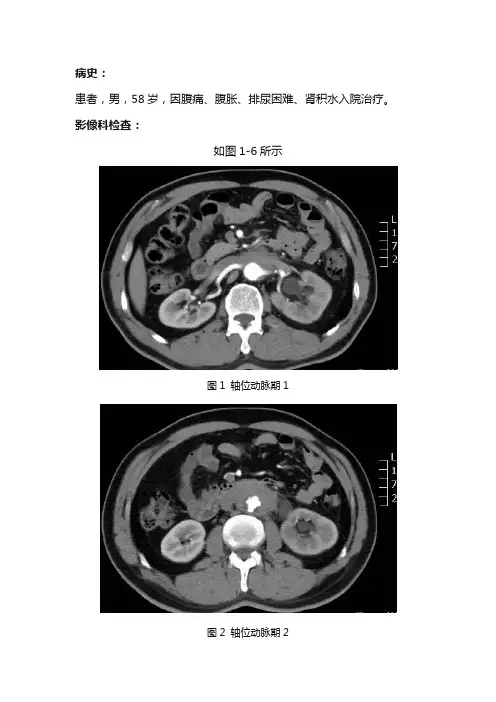

病史:患者,男,58岁,因腹痛、腹胀、排尿困难、肾积水入院治疗。

影像科检查:如图1-6所示图1 轴位动脉期1图2 轴位动脉期2图3 静脉期1图4 静脉期2图5 延迟期1图6 延迟期2基础解剖影像:图7 CT门脉期胰腺水平图8 CT门脉期胰腺水平腹膜后彩色示意图图9 CT门脉期肾脏水平图10 CT门脉期肾脏水平腹膜后彩色示意图图11 CT门脉期肾门水平图12 CT门脉期肾门水平腹膜后彩色示意图图13 CT门脉期结肠水平图14 CT门脉期结肠水平腹膜后彩色示意图图7-14所示分别为正常成人腹部增强门脉期胰腺水平、肾脏水平、结肠水平轴位图像及腹膜后彩色示意图(节选自《CT与MRI断层解剖学袖珍图谱-心胸腹盆》),CT图像中因口服对比剂,胃肠道内可见高密度对比剂影,彩色示意图中黄色区域为腹膜后区域,包括胰腺、双肾等组织器官。

图1图2图3图4图5图6图1-6所示腹部轴位:腹膜后肠系膜根部包绕腹主动脉可见不规则形软组织密度影(黄色箭头),12.5cmX3.2x16.3cm,边界欠清,密度欠均匀。

增强可见病变轻度尚均匀延迟强化,包绕双肾动静脉及左肾输尿管,血管走行僵直,管壁略窄,左侧肾盂肾盏及上段输尿管扩张(蓝色箭头)。

腹主动脉管壁不规则增厚,可见龛影形成(考虑主动脉粥样硬化、穿透性溃疡)。

影像诊断:腹膜后占位病变,考虑腹膜后纤维化,不除外其他恶性病变。